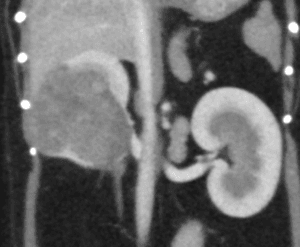

犬の副腎腫瘍は、大きく臨床症状を示す「機能性腫瘍」と、症状を示さず画像検査で偶発的に見つかる「副腎偶発腫」に分類されます。副腎は外側の皮質からコルチゾールなどのステロイドホルモンを、内側の髄質からカテコラミンと呼ばれるホ […]